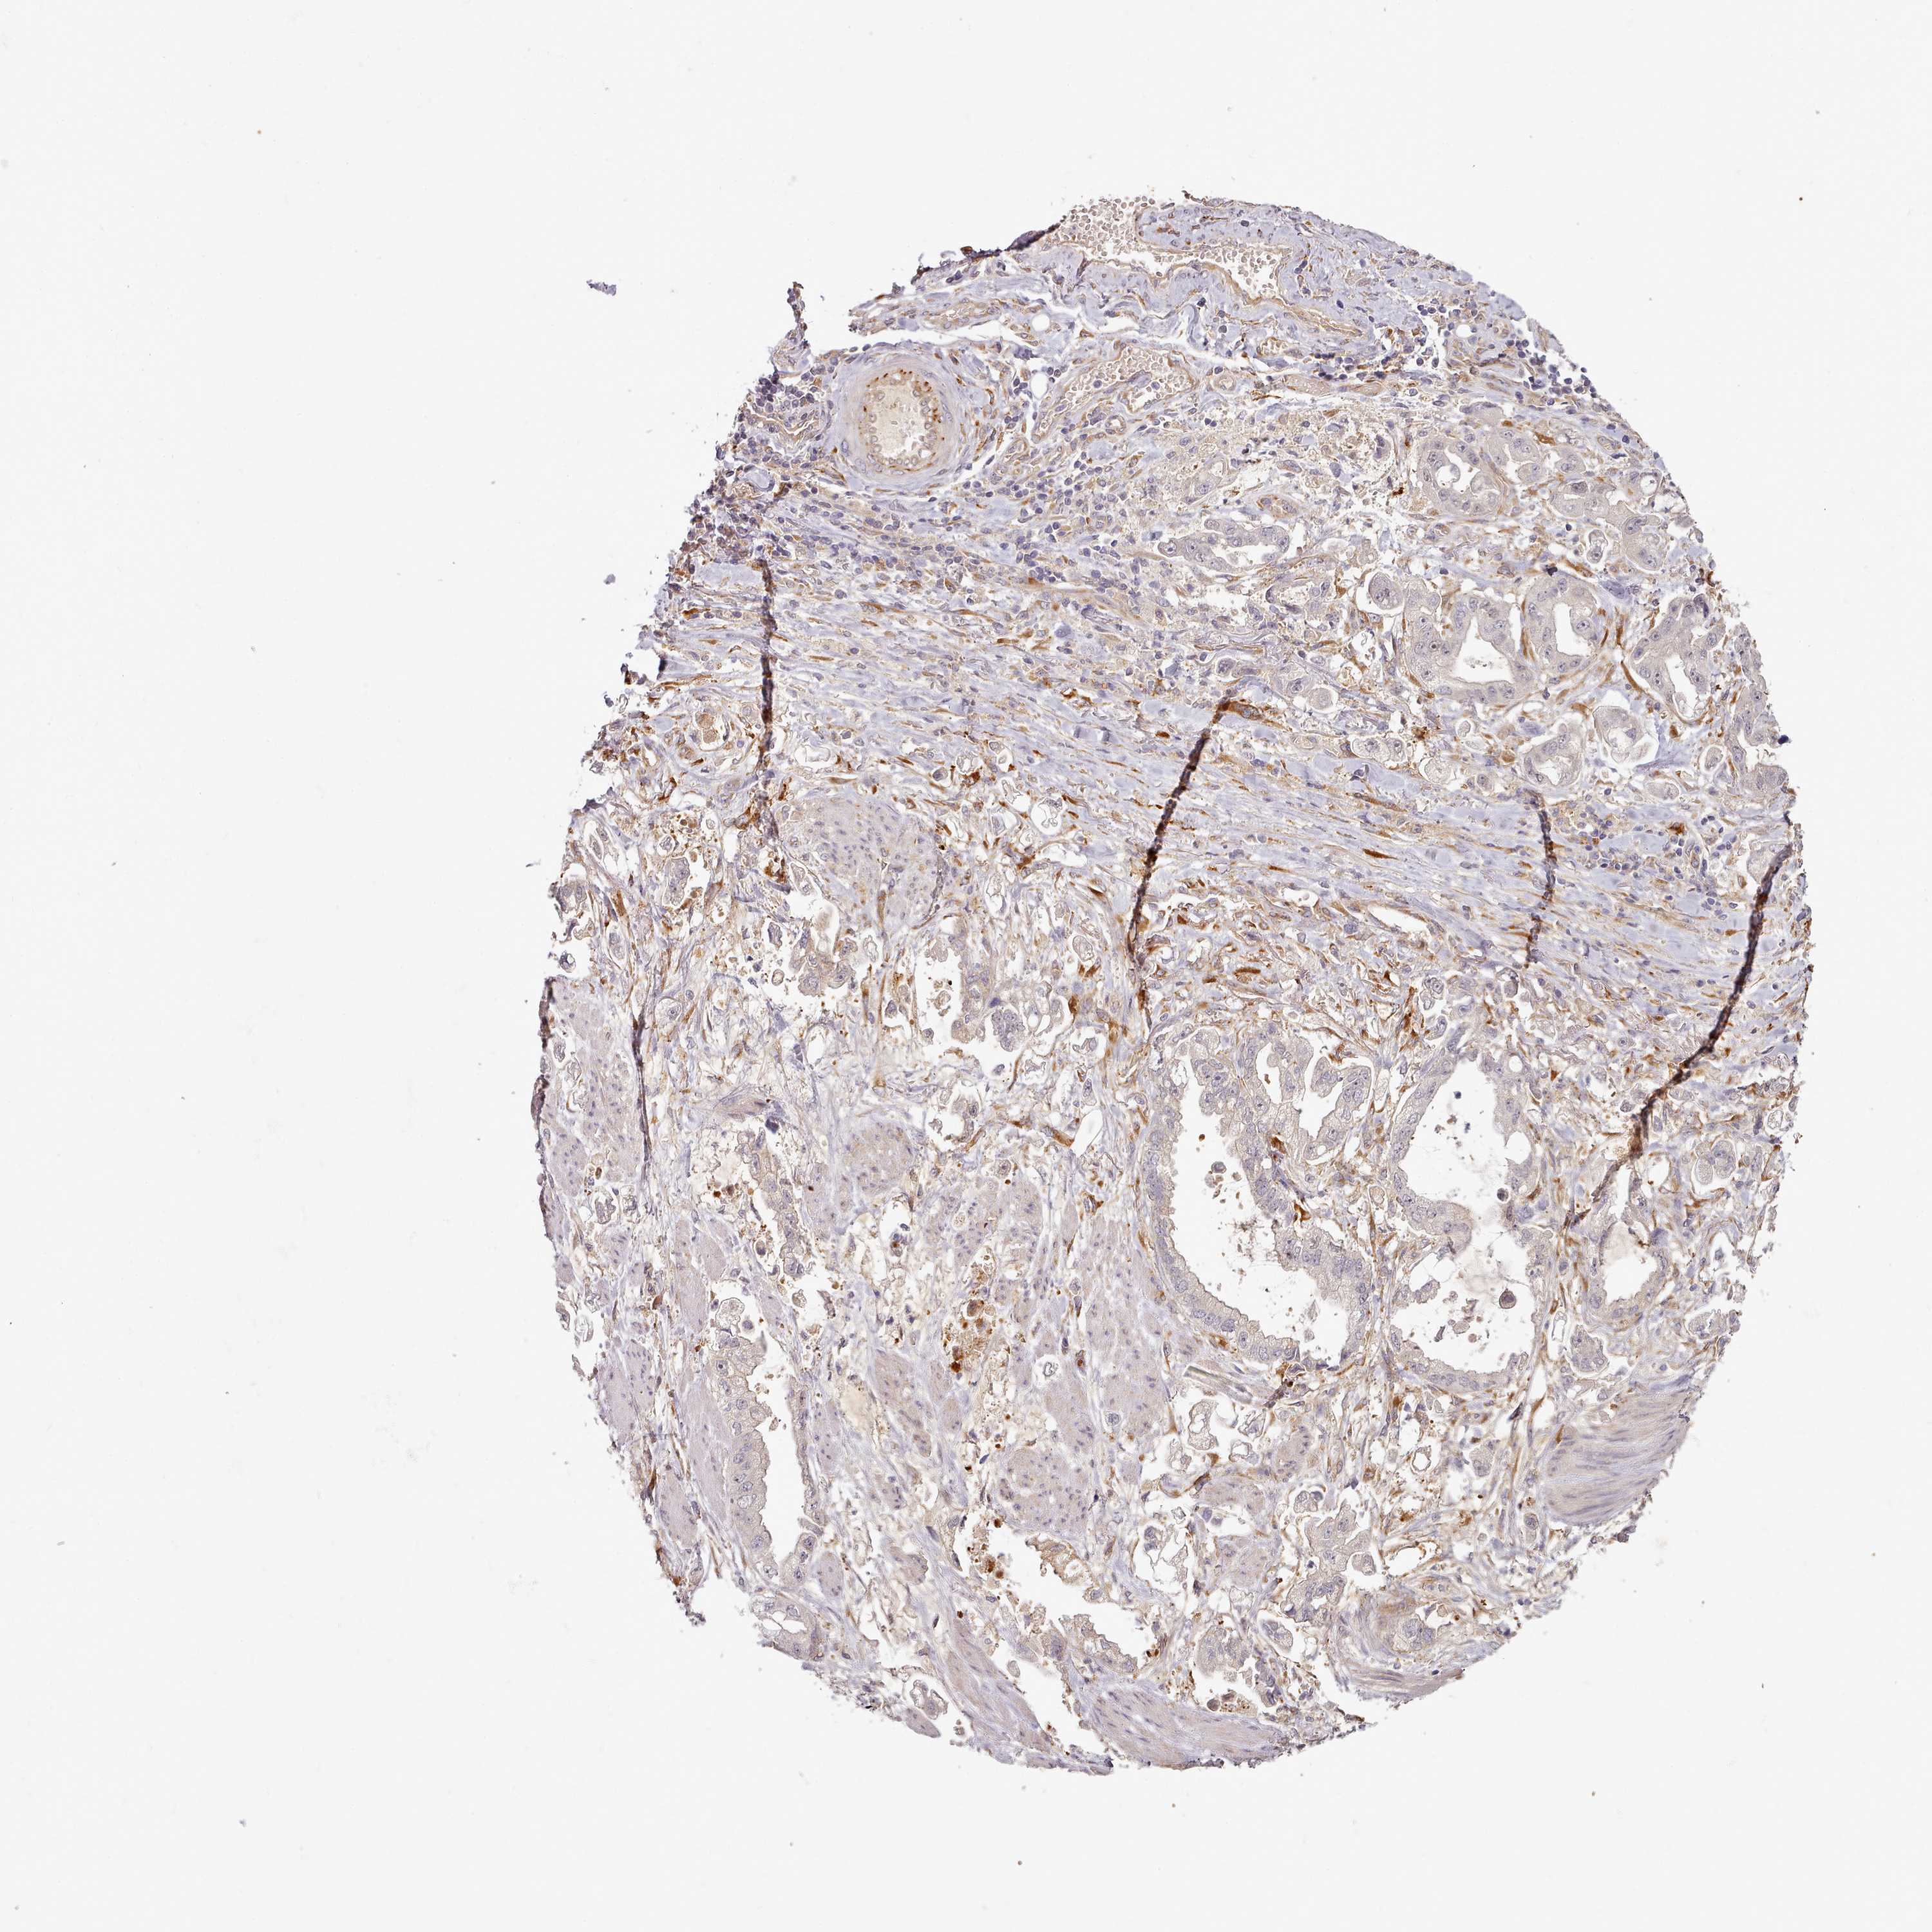

STOMACH CANCER - Protein expressioni

A mouse-over function shows sample information and annotation data. Click on an image to view it in a full screen mode. Samples can be filtered based on level of antibody staining by selecting one or several of the following categories: high, medium, low and not detected. The assay and annotation is described here.

Note that samples used for immunohistochemistry by the Human Protein Atlas do not correspond to samples in the TCGA dataset.

Antibody stainingi

Antibody staining in the annotated cell types in the current human tissue is reported as not detected, low, medium, or high, based on conventional immunohistochemistry profiling in selected tissues. This score is based on the combination of the staining intensity and fraction of stained cells.

Each image is clickable and will lead to virtual microscopy that enables deeper exploration of all samples and also displays staining intensity scores, fraction scores and subcellular localization as well as patient and tissue information for each sample.

Antibody HPA038604

Antibody CAB025607

Staining

High

Medium

Low

Not detected

Intensity

Strong

Moderate

Weak

Negative

Quantity

>75%

75%-25%

<25%

None

Location

Nuclear

Cytoplasmic/membranous

Cytoplasmic/membranous,nuclear

Adenocarcinoma, NOS